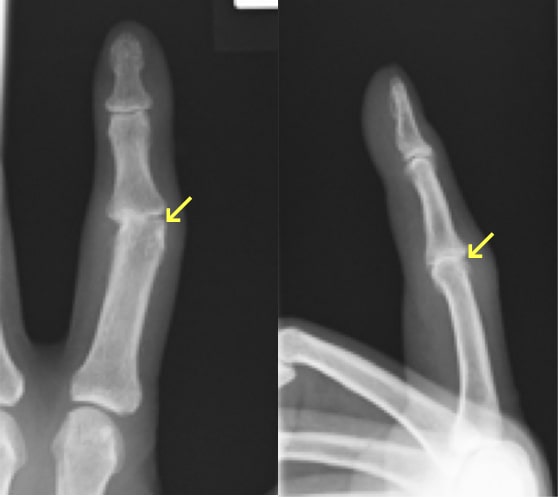

指骨・中手骨骨折

中手骨骨折 術前・術後写真

中手骨骨折術前・術後

指骨・中手骨骨折写真

基節骨変形癒合により指交差現象が出現

(握ると環指が小指に重なる)

原因

壁を殴ってしまったり、転倒した際に強打してしまったりして生じます。

症状

手や指が腫れて、痛くて動かせなくなります。変形を認める場合もあります。

治療方針

転位やズレの程度で治療方針を決めます。指の骨折の治療で重要なことは長期間固定をして拘縮を作らないことです。ほんの数週間の外固定により骨折部以外の関節も固くなってしまい、また少しの変形であっても指を握った時に重なったりする重篤な後遺症が生じることがありますので注意が必要です。手外科専門医にかかることをお勧めします。